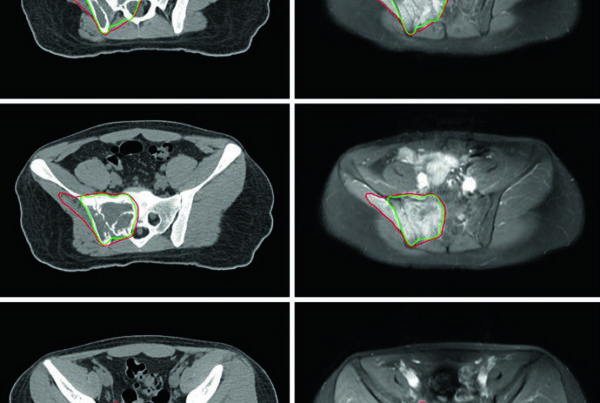

Uma das grandes virtudes do compêndio é sua abrangência. Para um mesmo sítio tumoral, as diretrizes oferecem restrições específicas para diferentes esquemas de fracionamento. Por exemplo, as recomendações para pulmão incluem tabelas separadas para regimes de 3, 4, 5, 8 e mais frações — eliminando a ambiguidade que ocorre quando se tenta interpolar restrições entre esquemas diferentes.

O documento inclui recomendações para sítios como cérebro, cabeça e pescoço, mama, pulmão, esôfago, estômago, pâncreas, fígado, reto, próstata, bexiga, ginecológico e coluna, entre outros. Essa abrangência é especialmente relevante para a prática diária de delineamento e setup em radioterapia, onde a padronização de restrições reduz variabilidade e melhora a consistência do cuidado.